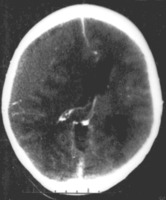

Epidural hematoma as seen on a CT scan with overlying skull fracture. Note the biconvex shaped collection of blood. There is also bruising with bleeding on the opposite side of the brain.

Epidural hematomas usually appear convex in shape because their expansion stops at the skull's sutures, where the dura mater is tightly attached to the skull. Thus, they expand inward toward the brain rather than along the inside of the skull, as occurs in subdural hematomas. Most people also have a skull fracture.[3]